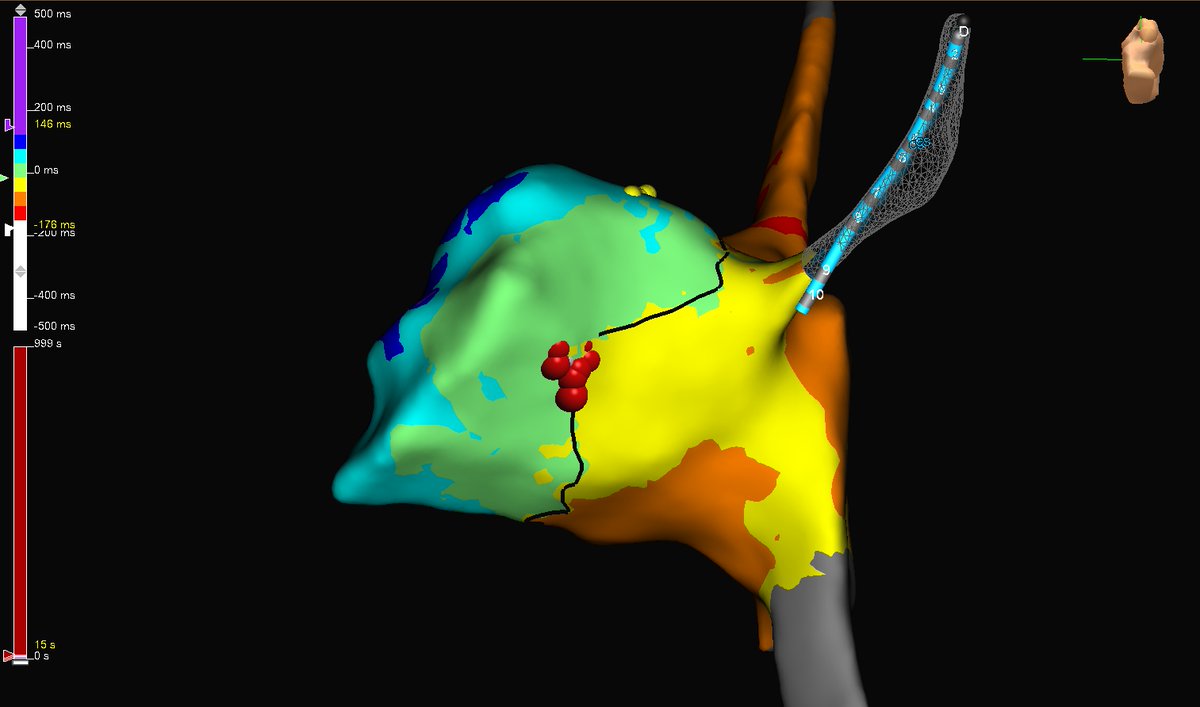

AVRT! Open window mapping of a concealed left lateral accessory pathway using the HD Grid. One burn term (1.3 seconds). #AbbottProud #MapMoreBurnLess #HDGrid #TactiFlex

SoFloAbbottEP's tweet image. AVRT! Open window mapping of a concealed left lateral accessory pathway using the HD Grid. One burn term (1.3 seconds).